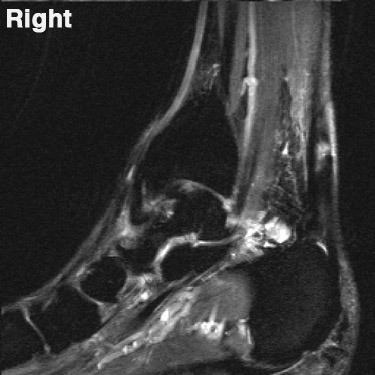

17. 족저근막염과 관련되어 MRI에서 관찰되는 것은 무엇인가?

족저근막염(Plantar fasciitis)은​ 족저골극(plantar enthesophyte)을 가지거나 가지고 있지 않은 족저근막의 근위 부착부에 인접한 곳에서 증가된 T2 신호를 보인다. 근막은 두꺼워질 수 있다. 예후가 불량한 경우는 종골에서 족저근막 부착부 인접 부위의 골수종을 볼 수 있다. (그림 47-3)

△ 그림 47-3. 발목 시상면 STIR 영상. 족저근막염을 가진 환자의 연부조직과 골수종을 보여준다.